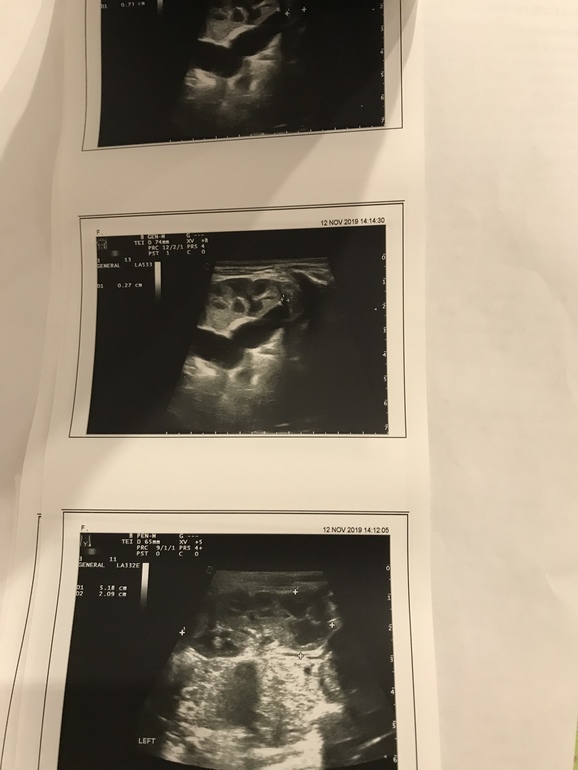

Мегауретер и удвоенная почка у дочки (2 месяца )

Это норма или срочно к врачу? Мегауретер